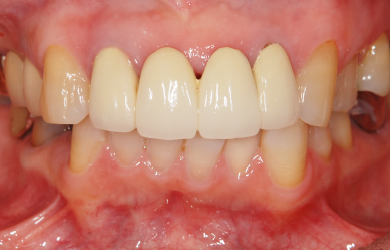

治療後

• 治療後